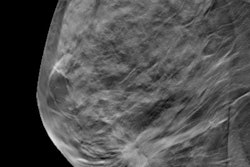

DBT has been shown to be more sensitive than conventional digital mammography in detecting breast cancer, making it a promising technology for screening. But increased sensitivity isn't always a benefit: It can lead to overdiagnosis or an early diagnosis that doesn't change a woman's prognosis, Pattacini and colleagues wrote.

The combination of digital mammography and DBT also found smaller cancers (< 20 mm) and more cancers in dense breast tissue than digital mammography alone. However, it also found more ductal carcinoma in situ (DCIS), the group noted.